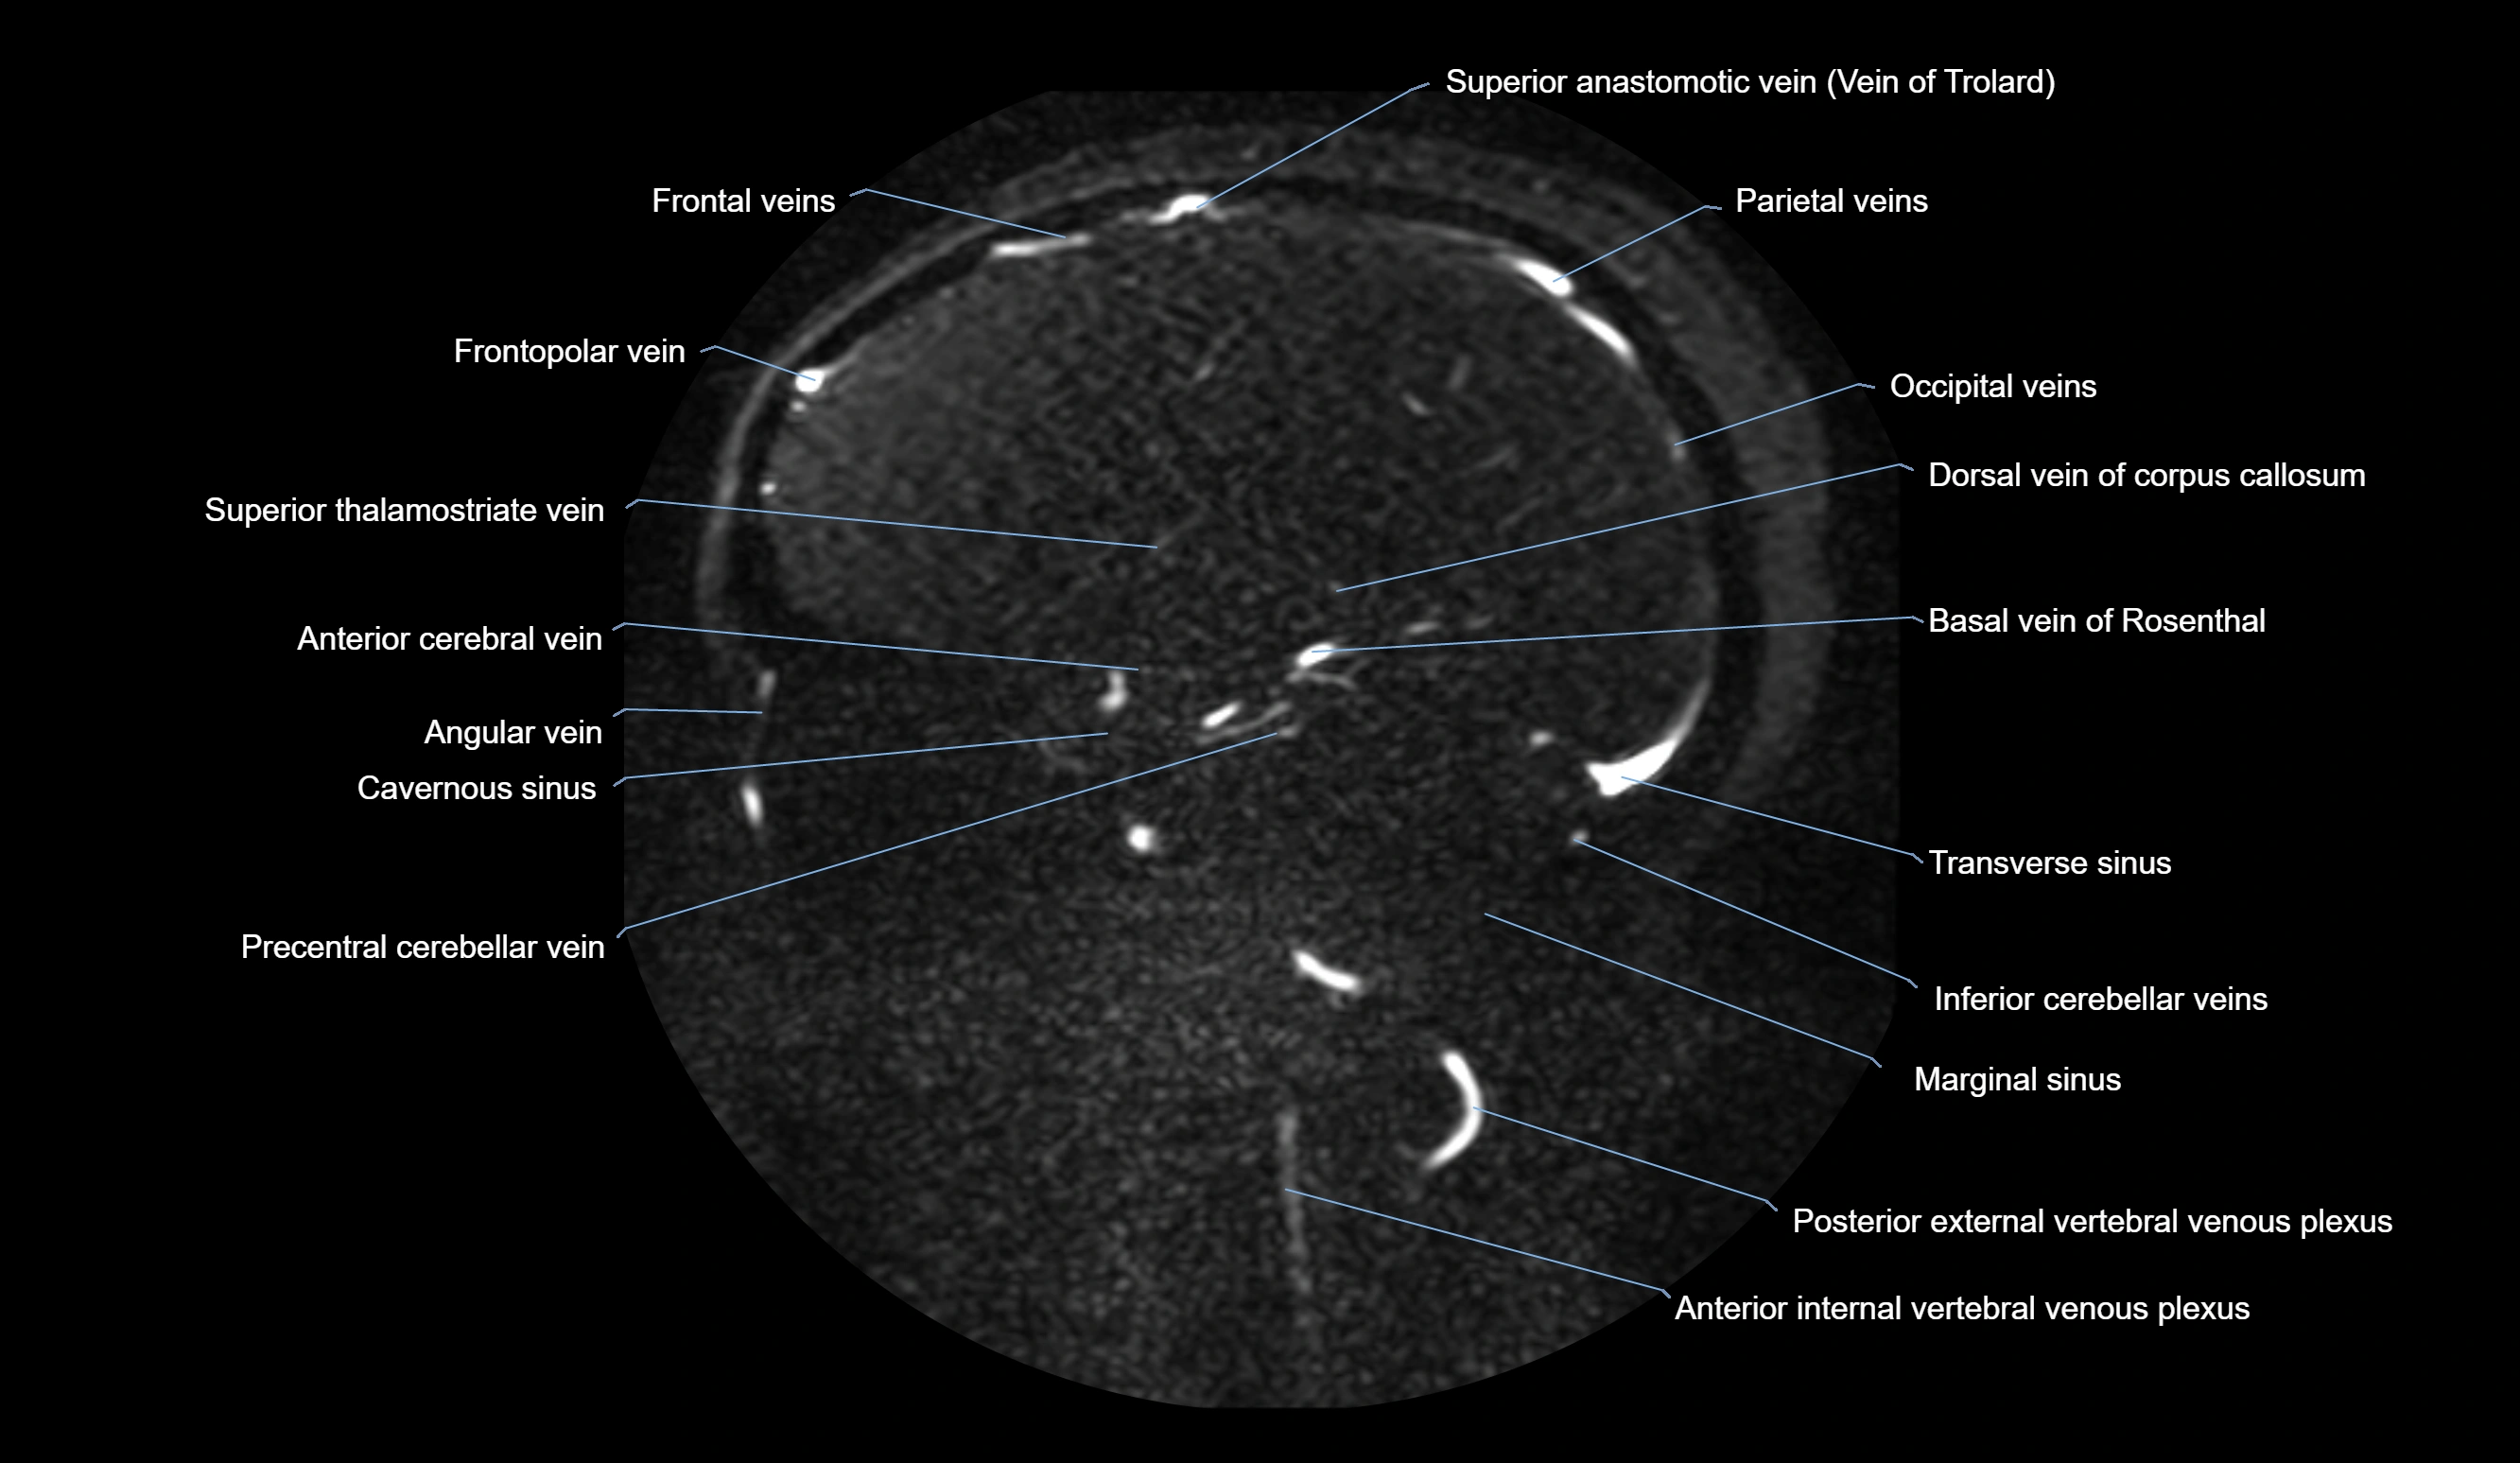

MR Venography (MRV):

• Time-of-flight (TOF) or contrast-enhanced MRV shows the angular vein as a bright enhancing venous channel

• Clearly demonstrates its continuity with the facial vein and superior ophthalmic vein

• MRV is highly useful in evaluating thrombosis, venous obstruction, or collateral venous drainage